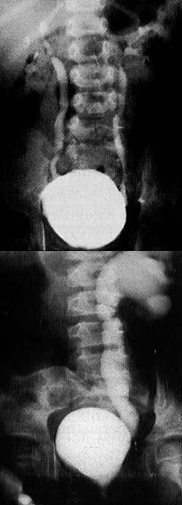

Il RVU è un fenomeno dinamico ed intermittente di risalita retrograda di urina (reflusso), di grado variabile, dalla vescica alla via urinaria superiore. Esiste una profonda differenza tra la condizione “primitiva”, geneticamente determinata e frequentemente associata ad un danno renale che nasce con il bambino (displasia renale) rispetto ad una condizione “secondaria” legata ad una alterazione funzionale vescicale o neurologica che può portare ad un danno pielo-nefritico acquisito (cicatrice renale–scar) ed irreversibile.